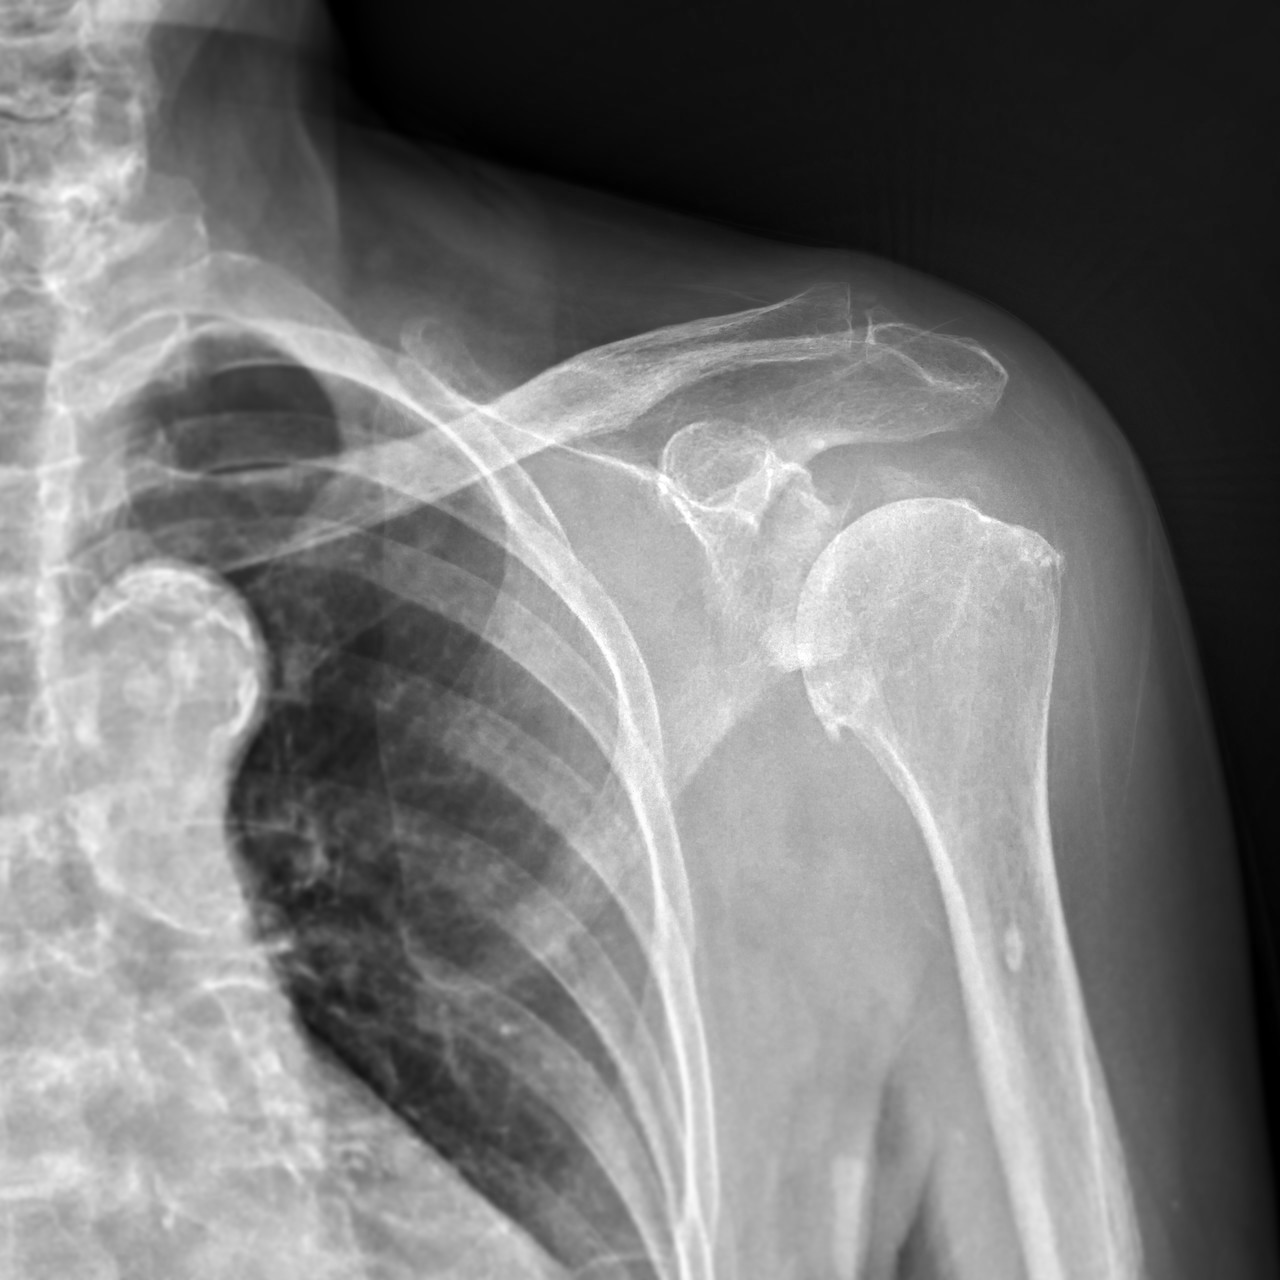

ROTATOR CUFF TEAR

회전근개 파열

반복적인 충격이나 자극이 가해져 회전근개가 파열되어

극심한 통증을 일으키는 질환을 말합니다.

어깨관절을 덮고 있는 네 개의 근육(극상근, 극하근, 견갑하근,

소원근)을 합쳐서 회전근개라고 하는데 4개의 회전근 중

특히 극상근의 파열 비율이 가장 높습니다.

회전근개에 발생한 염증과 손상은 어깨관절 통증의

가장 흔한 원인 중 하나입니다.

정밀진단

원장님과 상담 후 X-ray, 초음파 등 정밀 장비를 이용하여 정확하게 분석한 후 해당 결과를 토대로 재상담을 진행